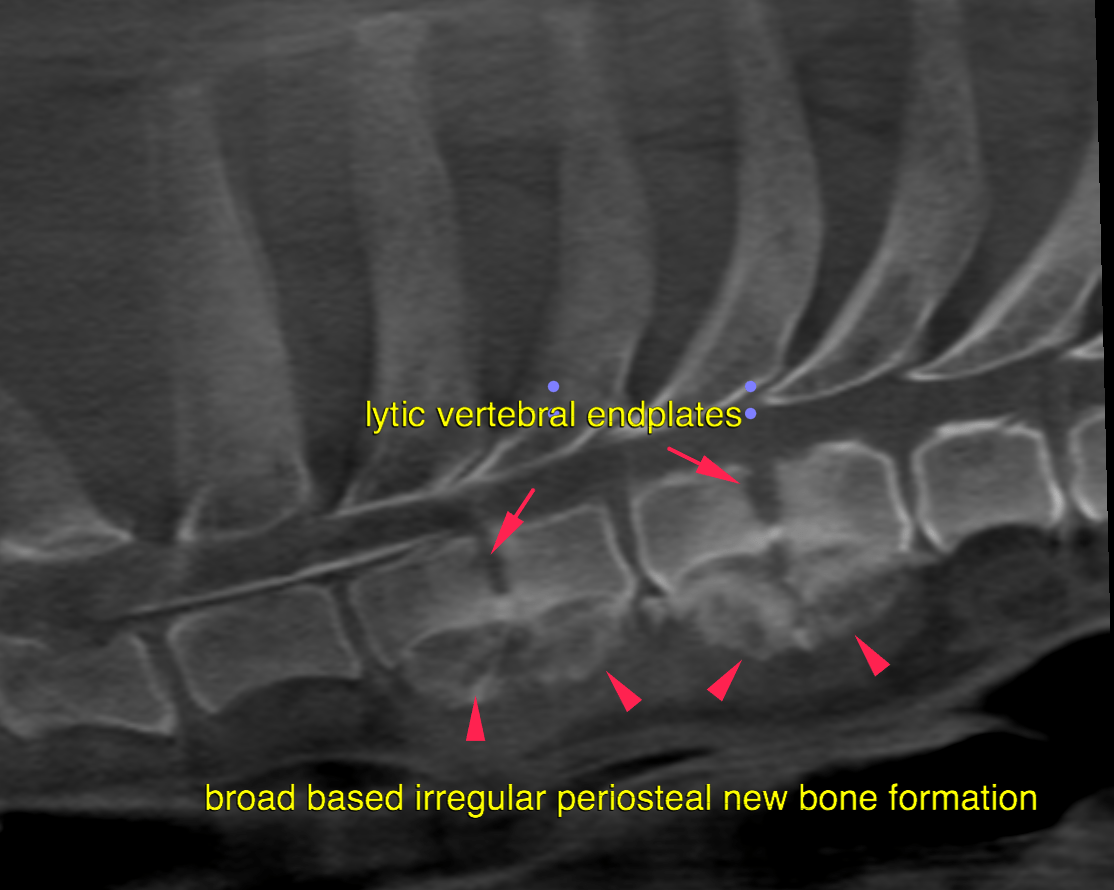

This 6 year old MN German Shepherd dog was diagnosed with hyphema, glaucoma and ocular trauma OD 3 week prior. Presented 2 days ago for ataxia and disorientation; CP deficits noted pelvic limbs. Chem: pre-renal azotemia.